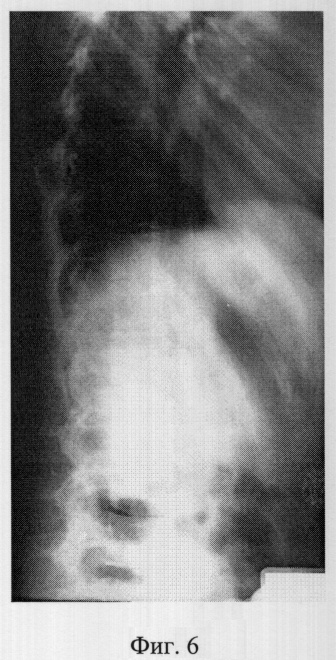

Фиг.6 – рентгенограмма в боковой проекции сколиотически измененного позвоночника больной M. до операции (грудная локализация);

В СарНИИТО ей была выполнена рентгенография в стандартных проекциях: фасная (фиг.5) и боковая (фиг.6) рентгенограммы.